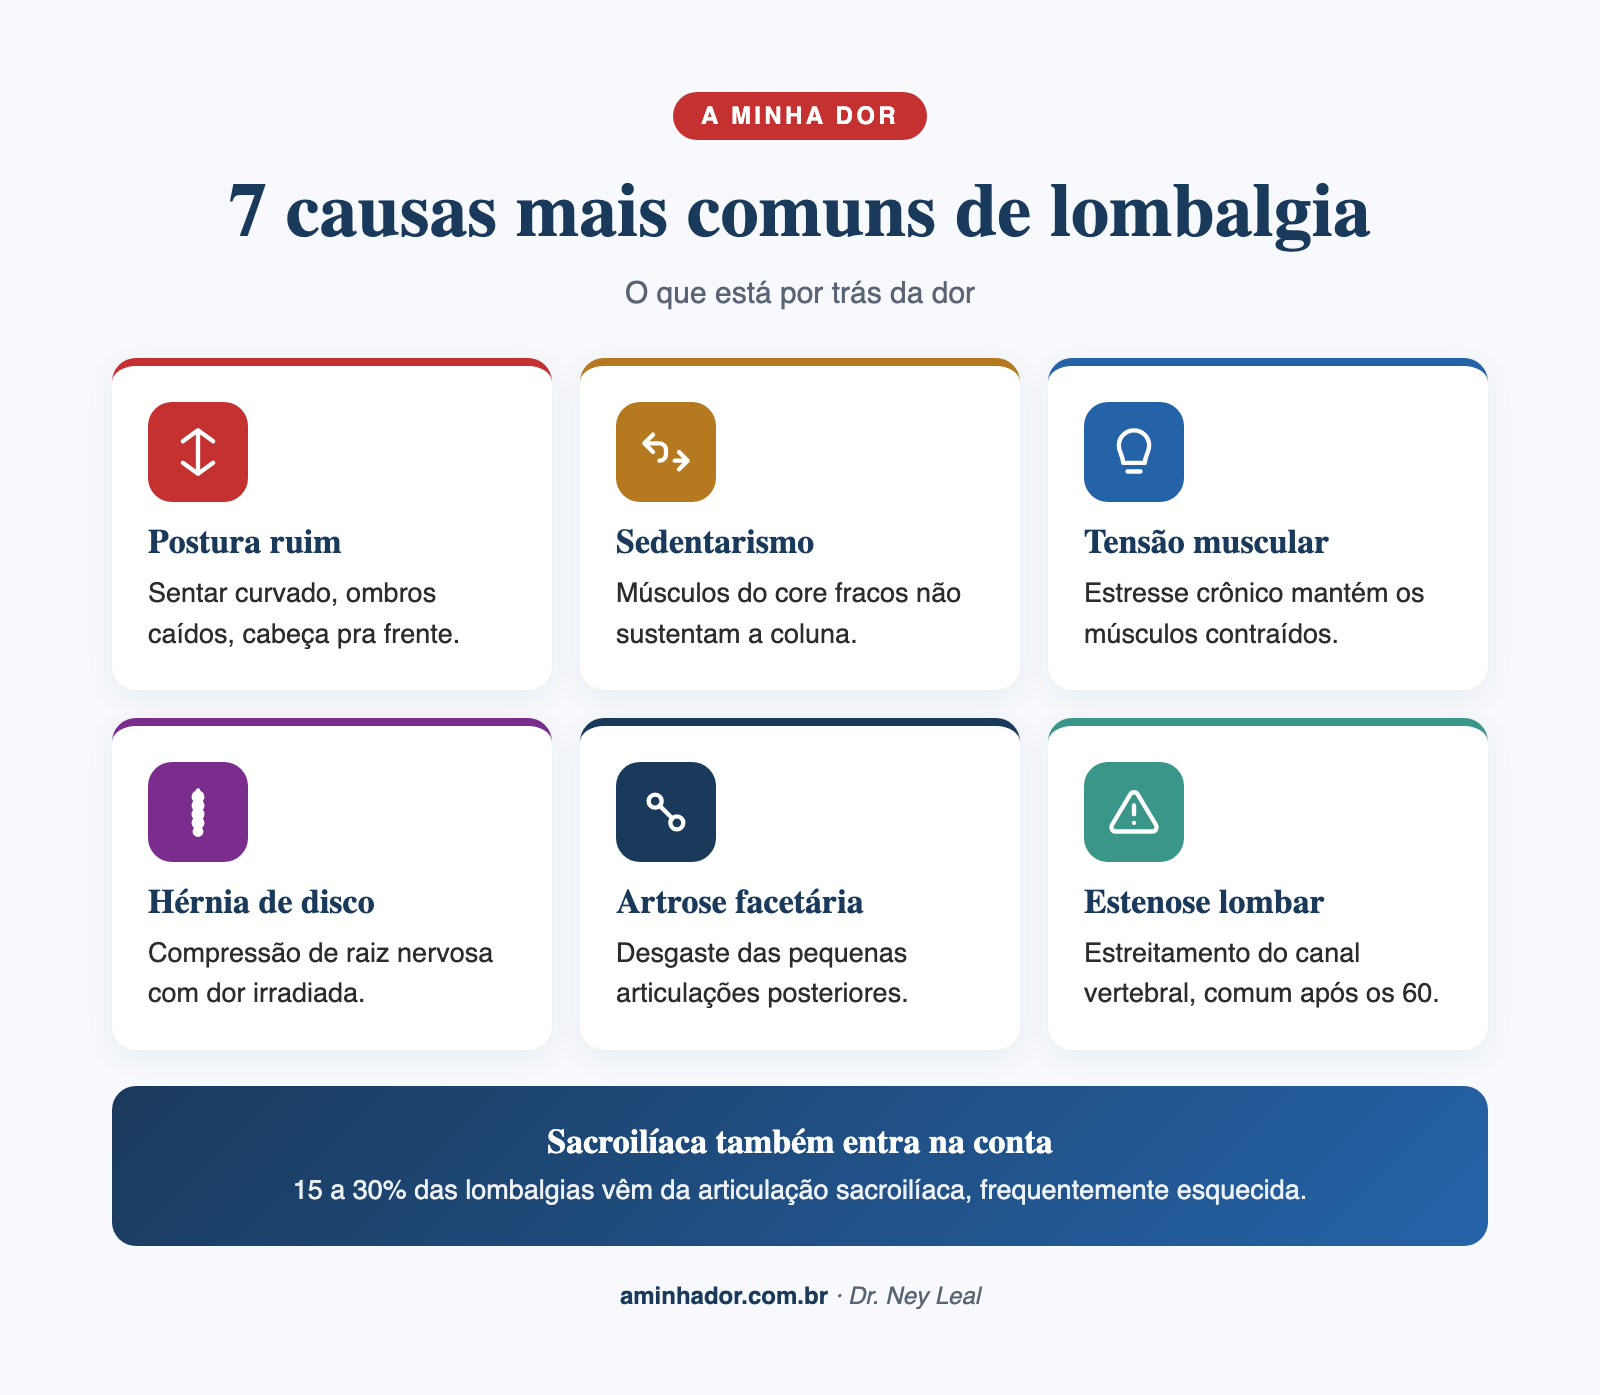

Causas da lombalgia

Causas mecânicas (mais comuns, cerca de 90% dos casos)[3]: distensão muscular, entorse ligamentar, degeneração dos discos gelatinosos que servem de almofada entre uma vértebra e outra, artrose das articulações, e por aí vai. Essas causas mecânicas não precisam de cirurgia na grande maioria dos casos.

Hérnia de disco: quando a parte de dentro, mais mole, do disco intervertebral se desloca e comprime um nervo. Pode causar a dor popularmente conhecida como ciática, que irradia pra perna como se um raio descesse. Mesmo assim, a maioria melhora sem cirurgia.

Estenose do canal medular: é o estreitamento do canal por onde passam os nervos dentro da coluna. Mais comum em pessoas acima dos 60 anos, pode ser causada por artrose nas articulações ou quando uma vértebra escorrega um pouco mais pra frente do que a de baixo, estreitando o canal por onde passam medula e nervos.

Dor na articulação sacroilíaca: essa articulação fica na base da coluna, entre o sacro e o osso ilíaco. A dor pode ser confundida com lombalgia, mas o tratamento é diferente.

Fatores de risco importantes: sedentarismo, obesidade, tabagismo, estresse emocional, posturas ruins por muito tempo, trabalhos com carga física intensa, e a própria anatomia do paciente. Costumo explicar no consultório: nossa coluna tem três curvas principais normais, a lordose do pescoço, a cifose na altura do tórax e outra lordose na região lombar. Isso é igual em praticamente todo ser humano.